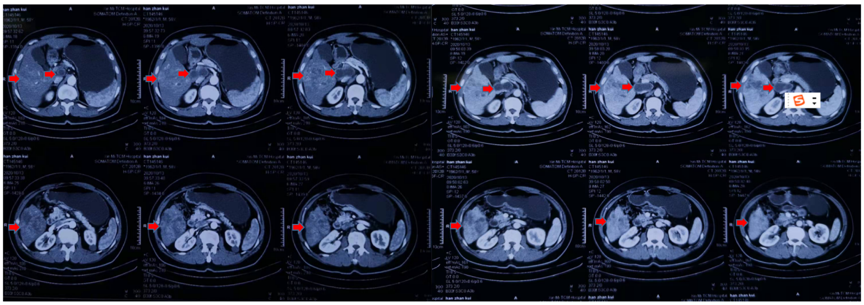

男性患者,58岁。2020年10月19日以“阵发性腹痛10天”为主诉入院。2020年10月13日外院上腹部增强CT提示肝右叶占位伴周围子灶,考虑HCC可能;腹膜后肿大淋巴结,考虑转移(图1)。

图1.2020年10月13日CT